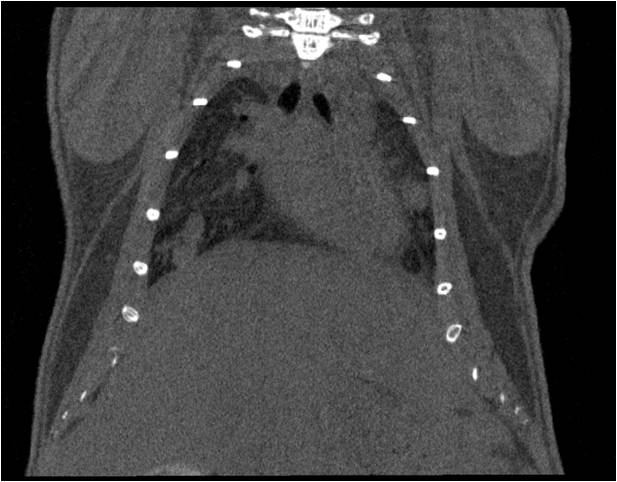

胸部和心血管的層析成像 胸部和心血管的3D圖像

心血管.jpg 心血管1.jpg